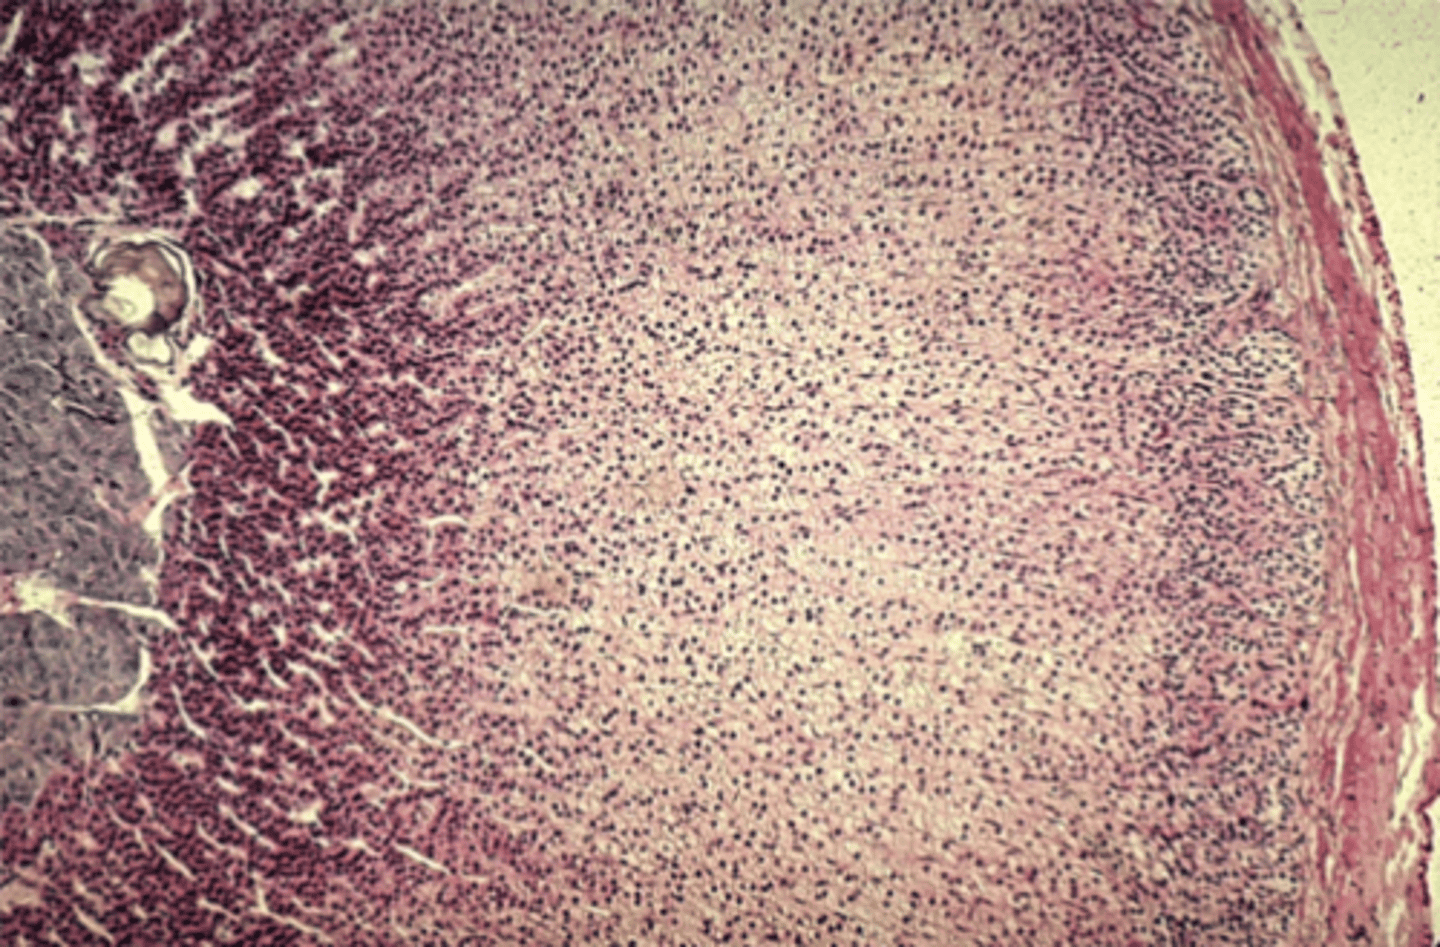

Lymph node

What is this?

Spleen

What is this?

White pulp in spleen

What is it pointing at?

Thymus

What is this?